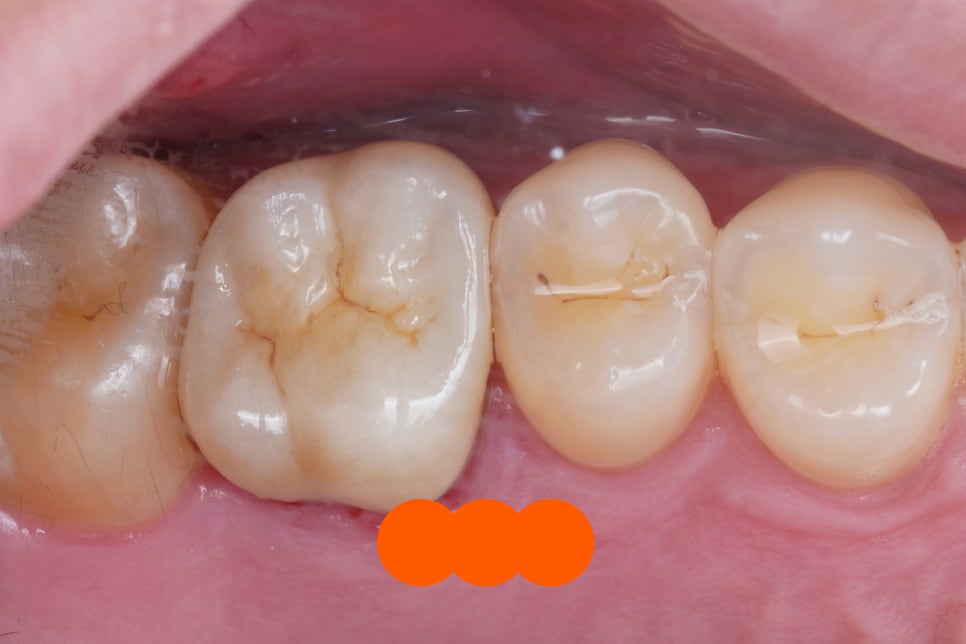

크라운을 벗겨내고

치아 내부를 관찰해봅니다.

굉장히 지저분하죠

크라운 내부, 치아의 외면은 물론

신경치료했던 치아 내부 역시

많이 오염되어있었습니다.

지르코니아 크라운 (큰어금니)

처음 사진과 비교하면 어떤가요

너무나도 자연치아와 비슷하게

잘 마무리 된 것 같습니다.

다시한 번 비교해볼까요?

전 후